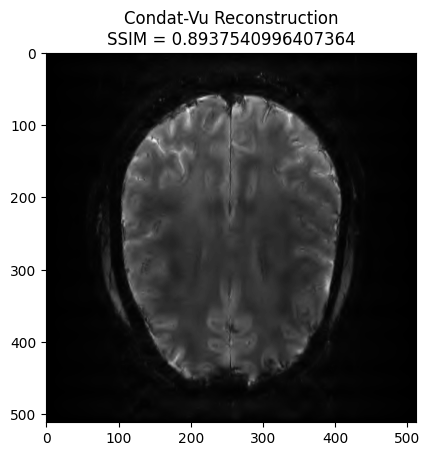

x_final, costs, metrics = reconstructor.reconstruct(

kspace_data=kspace_obs,

optimization_alg='condatvu',

num_iterations=100,

)

image_rec = np.linalg.norm(x_final, axis=0)

recon_ssim = ssim(image_rec, image)

plt.imshow(np.abs(image_rec), cmap='gray')

plt.title('Condat-Vu Reconstruction\nSSIM = ' + str(recon_ssim))